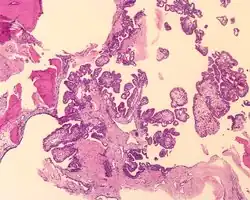

Tumors range from several millimeters up to 10 cm, with larger tumors more frequently seen in older patients. If the tumor is bilateral, it is almost always seen in a VHL patient. The tumor destroys the mastoid air spaces and extends into the middle ear and/or posterior cranial fossa.[1][3]

The microscopic appearance shows an unencapsulated, destructive growth, remodeling and invading bone. The tumor is arranged as simple, broad, non-complex papillary projections without large cystic spaces. The spaces are often fluid filled, have extravasated erythrocytes and/or inspissated material. The cells are cuboidal, usually single layered along the papillary structures, showing indistinct cell borders. The nuclei are round and hyperchromatic.[1][3][10][11]